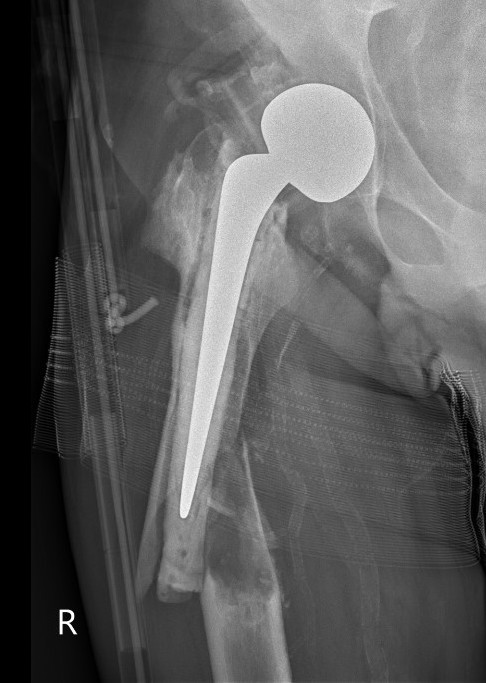

Type B1: Fracture around stem, likely well fixed

Stability

- 45 presumed type B1 periprosthetic fractures

- in 20% the femoral component was unstable

Management

ORIF with locking cable plate and +/- Cortical strut allograft